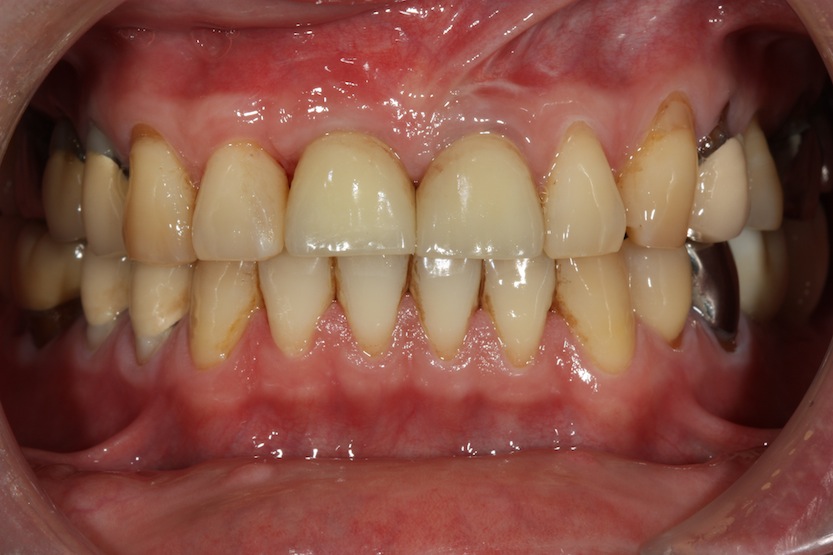

在牙齒#11 的位置是一個歷史悠久的單顆活動假牙,而且有趣的是客戶有嚴重的磨牙,磨到他自己睡覺會被吵起來,看門牙切端的形態就知道。好吧,看到這種齒槽脊,這種案例,報著一絲希望,轉給 Dr. Johnny 張 看看吧,本來預期做幫他做三顆的牙橋也 ok 啦,何必讓自己睡不著覺?

不管如何,九個月後,客戶回到 tof 的手中,裝好了 screw retained 的臨時假牙的樣子:

有趣的是,the mother nature 不僅在塑造牙齦,也利用客戶晚上會磨牙(bruxism)的機會每天在臨時假牙上雕琢出 tof 未來所要給客戶的門牙切端型態,不信的話,上下對照看看 patient 原來已經磨了十幾年的牙齒切端型態(下圖),和上圖臨時假牙的切端,是不是一模一樣?

完成圖及側方運動時的 occlusal design:

下圖:術後三個月回診照片,可見 cenral incisor 的 inter-dental papilla 已經長回來了。